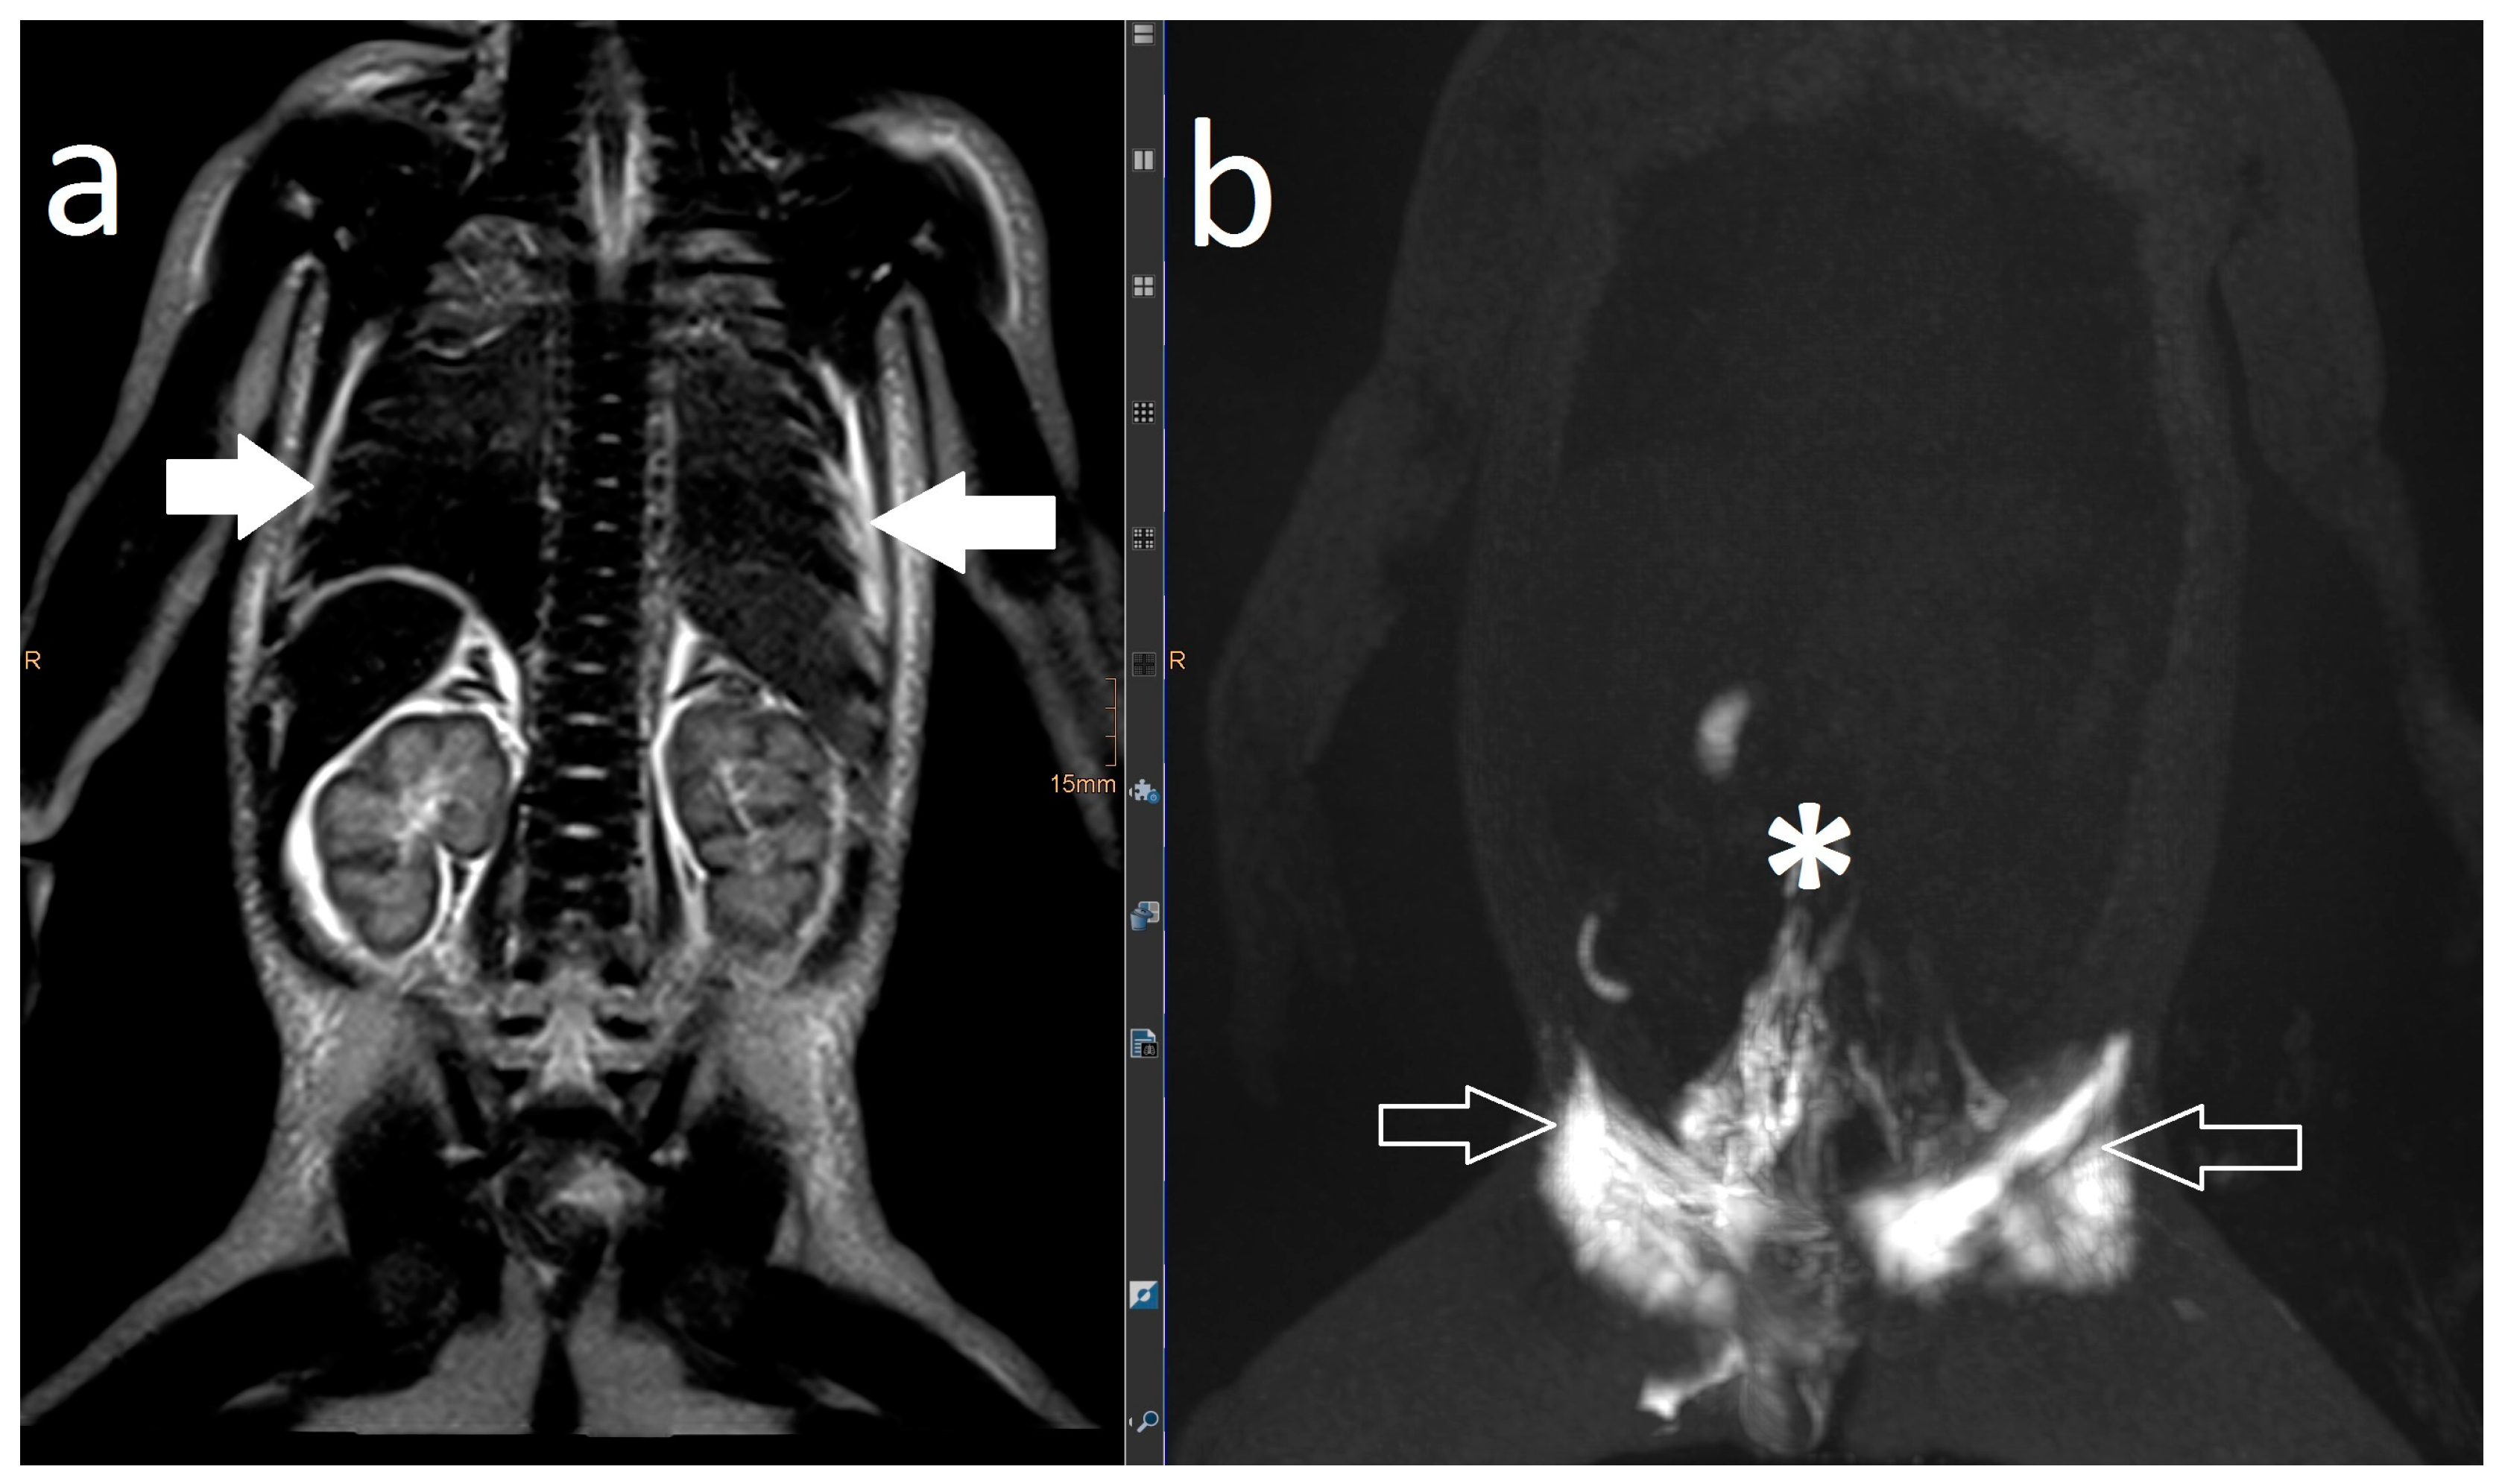

Lymphatic leak (marked with arrow).

Postoperative chylothorax was classified as previously introduced by Dori et al. based on dynamic contrast MR lymphangiography and intranodal lymphangiography and are described as traumatic leak (Figure 3), pulmonary lymphatic perfusion syndrome (abnormal pulmonary lymphatic flow from the thoracic duct toward the lung parenchyma through abnormal lymphatic networks in the chest and/or lymphatic perfusion of the mediastinum) (Figure 4) or central lymphatic flow disorders (abnormal central lymphatic flow, effusion in more than one compartment and the presence of dermal backflow) (Figure 5a,b) [9].

Figure 5.

Central lymphatic flow disorders: abnormal central lymphatic flow, effusion in more than one compartment (a, arrows point to thoracic compartment) and the presence of dermal backflow (b, see arrows, * shows a stop in contrast movement).